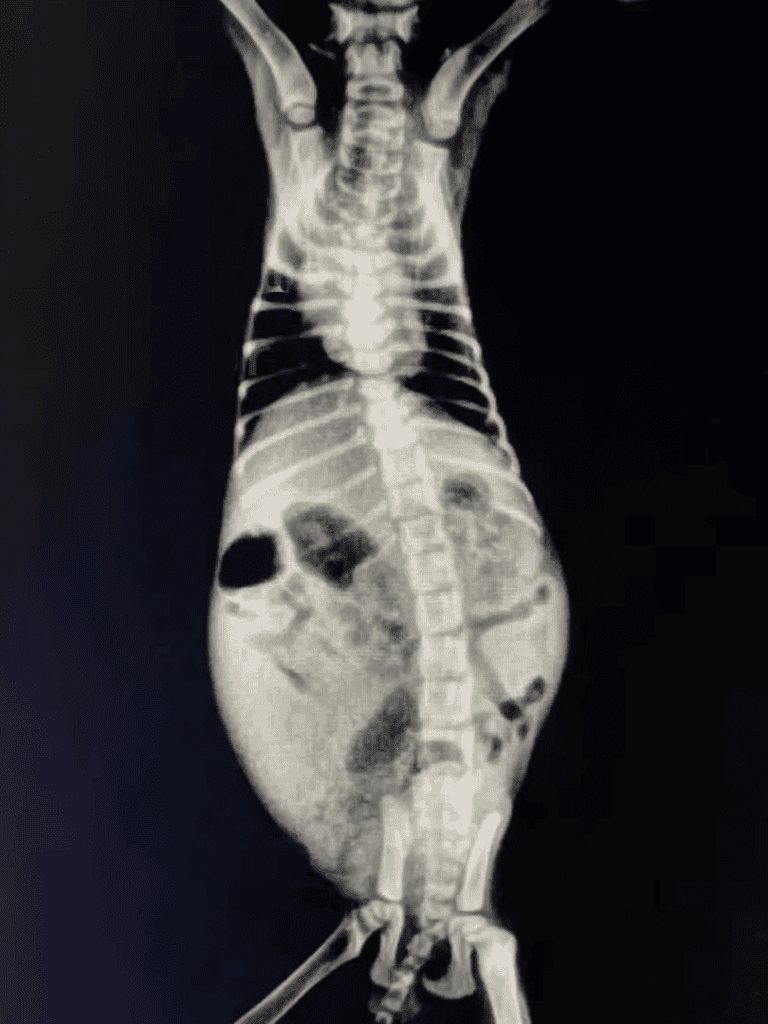

Taking a gentle approach, the girl rushed Jiuwan to the vet once more. An X-ray showed that his discomfort was due only to trapped gas.